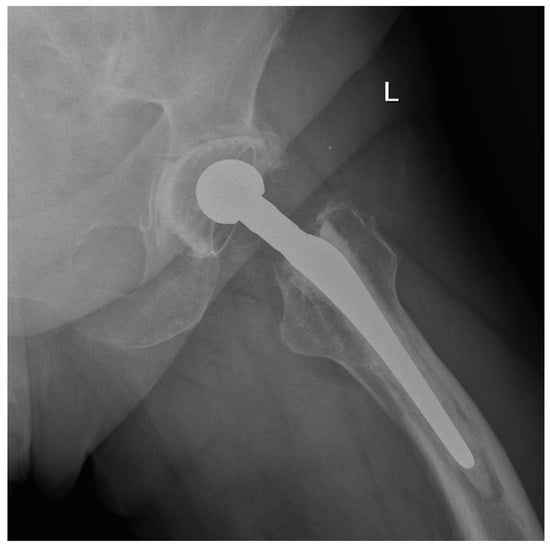

We observed a positive correlation between the increase in the mean oxidation index (OI) of the bearing surface of the inlays and the extent of periacetabular osteolysis classified according to the Paprosky scale (R = 0.44; p = 0.011). The most commonly revised types were 3A and 2B: 12 out of 33 samples (36.36%) were classified as type 3A, and 7 out of 33 samples were classified as type 2B (21.21%) according to Table 2. Mean oxidation index values for each type are, respectively, presented in Table 3. Figure 1 illustrates the differences in oxidative indices between the control sample and selected samples from groups 1 and 3B. Attention should be paid to the difference in the spectrum range of 1685–1745 cm−1. Representative X-ray images of patients depicting the extent of osteolysis based on the Paprosky scale can be seen in Figure 2, Figure 3 and Figure 4.

Figure 3. Periacetabular osteolysis classified as Paprosky 2B.